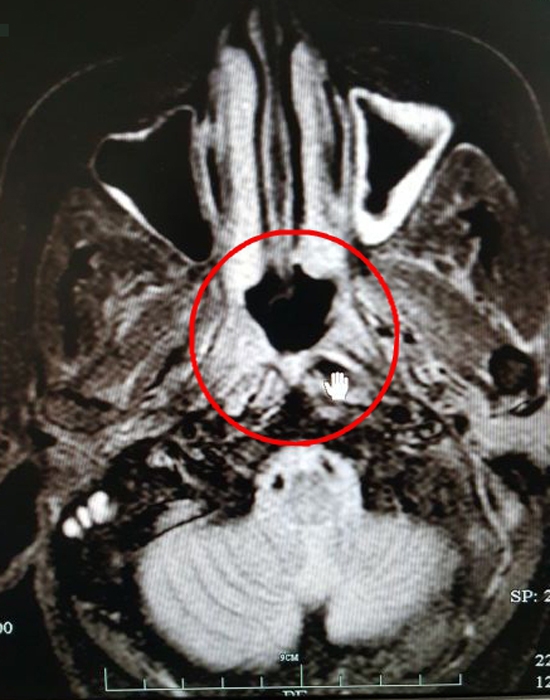

放療后的CT影像(紅圈處為病灶)

??? 目前,吳大姐鼻咽部的腫塊已經(jīng)明顯消失,治療效果明顯。